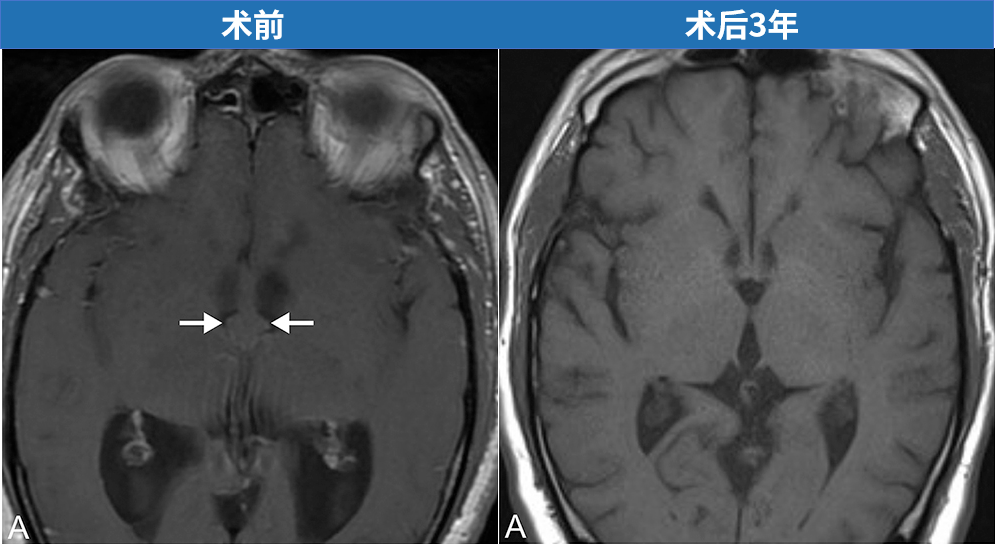

INC通过微创骨孔,成功取出胶样囊肿。一名55岁男性患者因进行性行走障碍与记忆力减退就诊,影像学检查提示脑积水。头部磁共振成像(MRI)进一步明确诊断为第三脑室胶样囊肿伴梗阻性脑积水。由世界神经外科学会联合会(WFNS)内镜委员会前主席Henry W. S. Schroeder(施罗德)教授主刀,为该患者实施神经内镜下第三脑室胶样囊肿切除术。术后三年随访显示囊肿完全切除,无复发征象。

术前磁共振成像清晰显示胶样囊肿,并导致双侧脑室积水。

术后3年复查MRI(T1加权轴位A,T2加权轴位B、冠状位C、矢状位D)显示囊肿全切,无残留与复发征象,脑室系统形态恢复良好。